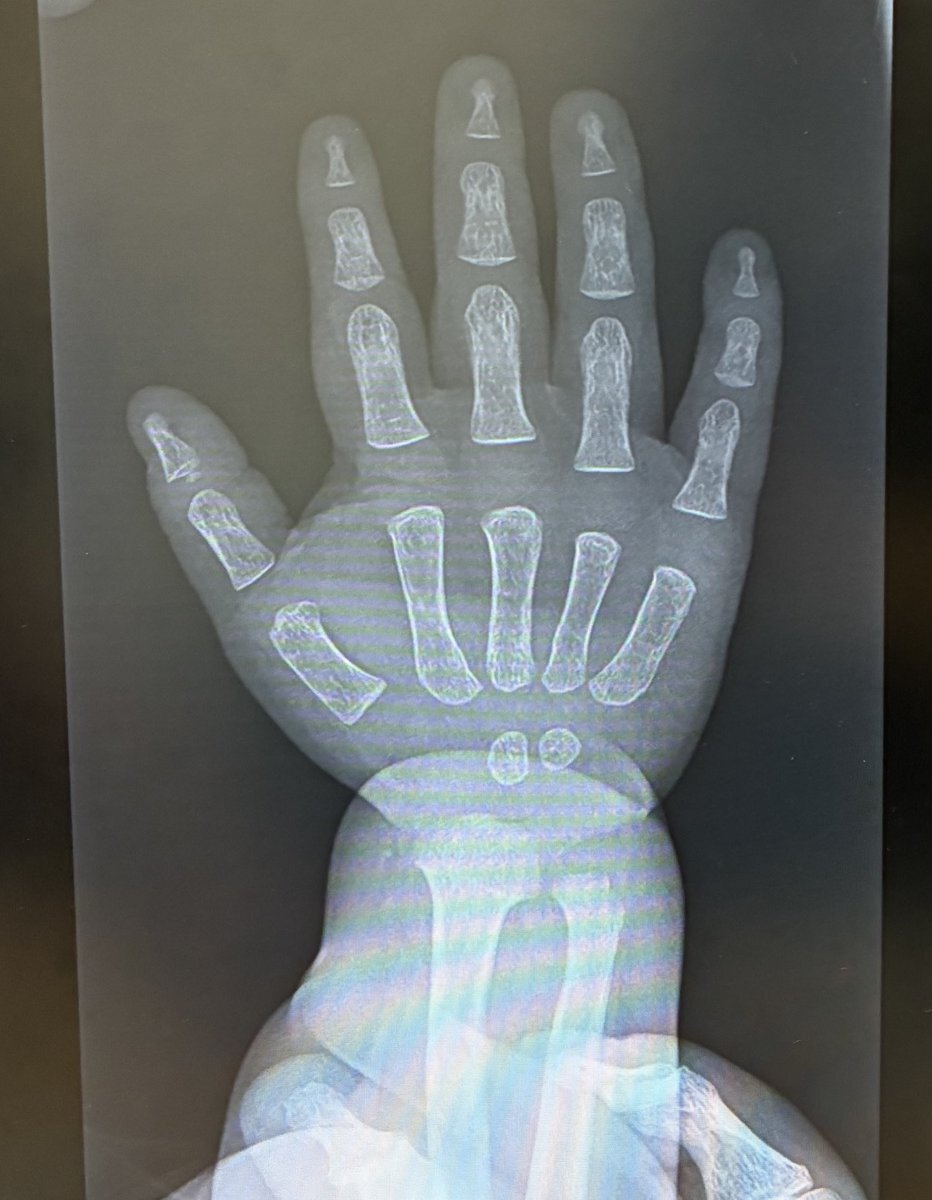

前に赤ちゃんのレントゲン話題になってたよね うちも撮る機会あってやっぱ可愛すぎた😍 さらには押さえつける看護師さんの手の骨まで写ってて感謝すぎた笑😂🙏🏻✨ pic.x.com/8tVfVmXHdc

あの小さな体でレントゲン台にちょこんと乗ってる姿、本当に愛おしいですよね。 看護師さんの手まで一緒に写るのも、守られている感じがして微笑ましい。 大変な検査のはずなのに、あの一枚には優しさと癒しが詰まってますね。